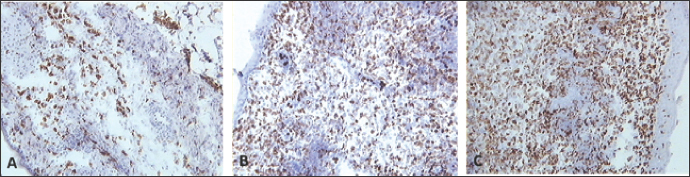

B cells

Skin sections were stained with the monoclonal antibody AV20 which recognizes Bu-1 on B cells (Rothwell et al., 1996) (Fig. 10). B cells increased in number from 2 dpv to reach a peak at 6–8 dpv at the site of vaccination in the skin, and then dropped in number from 10 dpv onwards (Fig. 11). At 2 and 4 dpv, B cells in skin sections were diffused. The formation of germinal centers (GC)-like structures started appearing at 6 dpv (Fig. 10). At 8 dpv onwards, almost all B cells were aggregated in these GC-like structures.

Fig. 10. Skin sections of birds stained with the monoclonal antibody AV20 6 days post inoculation with (A) PBSa, (B) PHA, and (C) FP9. Positive staining for B cells appeared brown. Arrows indicate formation of GC-like structures (100x magnification).

B cells were not present in normal human skin (Bos et al., 1987). After vaccination, there was an aggregation of B cells at the site of vaccination. After antigen challenge, GC is formed within the secondary lymphoid organs (lymph nodes, Peyer’s patches, spleen, or tonsils), and from the present experiment, GC-like structures were formed in the skin tissue too (Fig. 10). At 2 and 4 dpv, B cells in skin sections were diffused. However, the formation of GC-like structures started at 6 dpv (Fig. 10). At 8 dpv onwards, almost all B cells were aggregated in these GC-like structures.